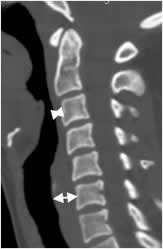

La alineación de la columna cervical en la proyección lateral, se determina trazando las líneas arcuatas. Son la vertebral anterior, vertebral posterior y la espinolaminar. (5). (Fig 3). Igualmente se deben tener en cuenta los espacios prevertebral y retrofaringeo, que se aumenta en casos de patología. El prevertebral se mide entre C1 y C4 y debe ser menor de 7 mm o el 30% del ancho del cuerpo vertebral. El retroesofágico entre C5 y C7 debe ser menor de 14 mm en los adultos y menor de 22 mm en los niños o igual al ancho del cuerpo vertebral. (5). (Fig 4A y B).

Fig 3. Líneas arcuatas.

Rx lateral. Línea vertebral anterior. (Blanca). Vertebral posterior (Negra) y espinolaminar (Roja).

Fig 4A. Espacios normales.

TAC reconstrucción sagital. Espacio prevertebral sobre C3 y retroesofágico, a nivel de C6.

Fig 4B. Desalineación.

Rx lateral. Anterolistesis post-traumática, con interrupción en las líneas vertebral anterior y posterior. Igualmente hay aumento del espacio retrofaringeo.